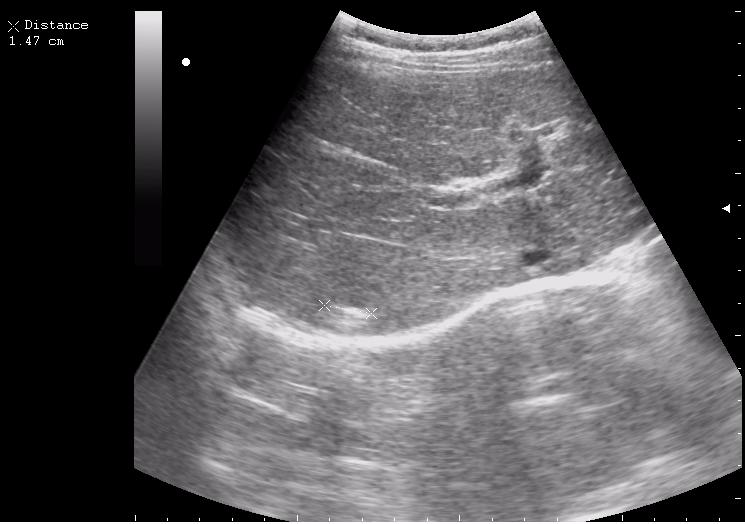

наезд большой черной Прады на маленькую (13кг) 5-летнюю девочку.

получает Медаксон, рабочая версия - изменение желчного пузыря вследствии травмы (шепотом - рекомендация хирургу сменить антибиотик)